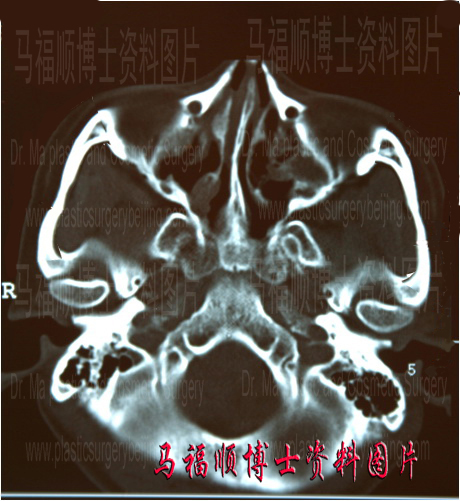

本研究使用PHILIP公司生产的Mx8000 多层螺旋CT,O2工作站。扫描参数:电压120KV,电流150mA,扫描层厚2.0mm,重建间隔1.0mm,螺距0.675。仰卧位、轴位连续扫描。图像处理技术:所有数据传至O2工作站,分别进行轴位、冠状位、矢状位的MPR,从不同角度观察颧弓的局部情况,重建轴位颧弓最大平面后直接测量颧弓长度和颧弓厚度。颧弓长度测量的起点为颧弓前拐点,止点为颧弓后拐点。同时进行SSD和VRT重建,在任意角度观察颧弓的关节结构,必要时进行关节解体处理,以便更好地观察颧弓情况。并将数据传递至工作站用UNISIGHT软件对图像进行重建,模拟截骨后图像,估计手术后的效果。见图。

左侧图片为术前颧骨颧怀平面的CT断层片,右侧为术前模拟颧骨颧弓整形后CT表现。

颧骨颧弓整形后实际CT断层片